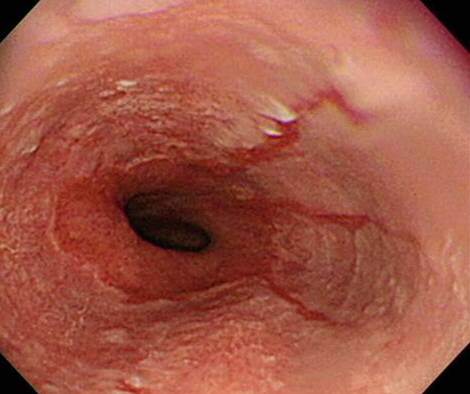

A 씨(45·여)는 최근 들어 식후 소화가 잘 안되고 체한 것처럼 가슴이 답답했다. 며칠 전 새벽에는 흉통과 함께 답답한 증상이 더 심해져 병원을 찾았다. 위내시경 검사 결과 ‘역류성 식도염’ 진단이 나와 위산분비 억제제 등을 투여받고 증상이 호전돼 귀가할 수 있었다.

역류성 식도염은 위산이나 위의 내용물이 역류해 식도 염증을 일으키는 질환이다. 국민건강보험공단 자료에 따르면 역류성 식도염 환자는 2009년 256만8000명에서 2013년 351만9000명으로 4년 동안 37% 증가했다. 경제활동인구인 40, 50대에서 주로 나타나고 있다.

인하대병원에서는 역류성 식도염의 감별 진단에 필요한 검사를 신속히 시행해 질환에 맞는 맞춤치료를 제공하는 시스템을 갖추고 있다. 또 역류성 식도염의 원인과 치료 및 향후 재발을 방지하기 위한 교육을 정기적으로 진행해 환자의 호응을 얻고 있다. 역류성 식도염은 위산분비를 강력히 억제하는 약물을 증상에 따라 4∼8주 투여해 치료할 수 있다. 약을 끊으면 높은 재발률을 보여 생활습관 개선이 필요하다. 역류성 식도염 예방을 위해서는 운동과 식이요법을 통해 체중을 줄이고 조이는 옷을 입거나 복압(복강 안의 압력)을 증가시키는 행위는 피하는 것이 좋다.

금주, 금연과 더불어 취침 전 음식 섭취를 피하고 역류를 악화시킬 수 있는 기름진 음식이나 카페인 음료는 피해야 한다. 역류성 식도염을 가볍게 여기고 방치하면 식도암으로 발전되거나 다른 합병증을 유발할 수 있기 때문에 증상이 느껴지면 병원을 찾아 검사받을 것을 권한다.